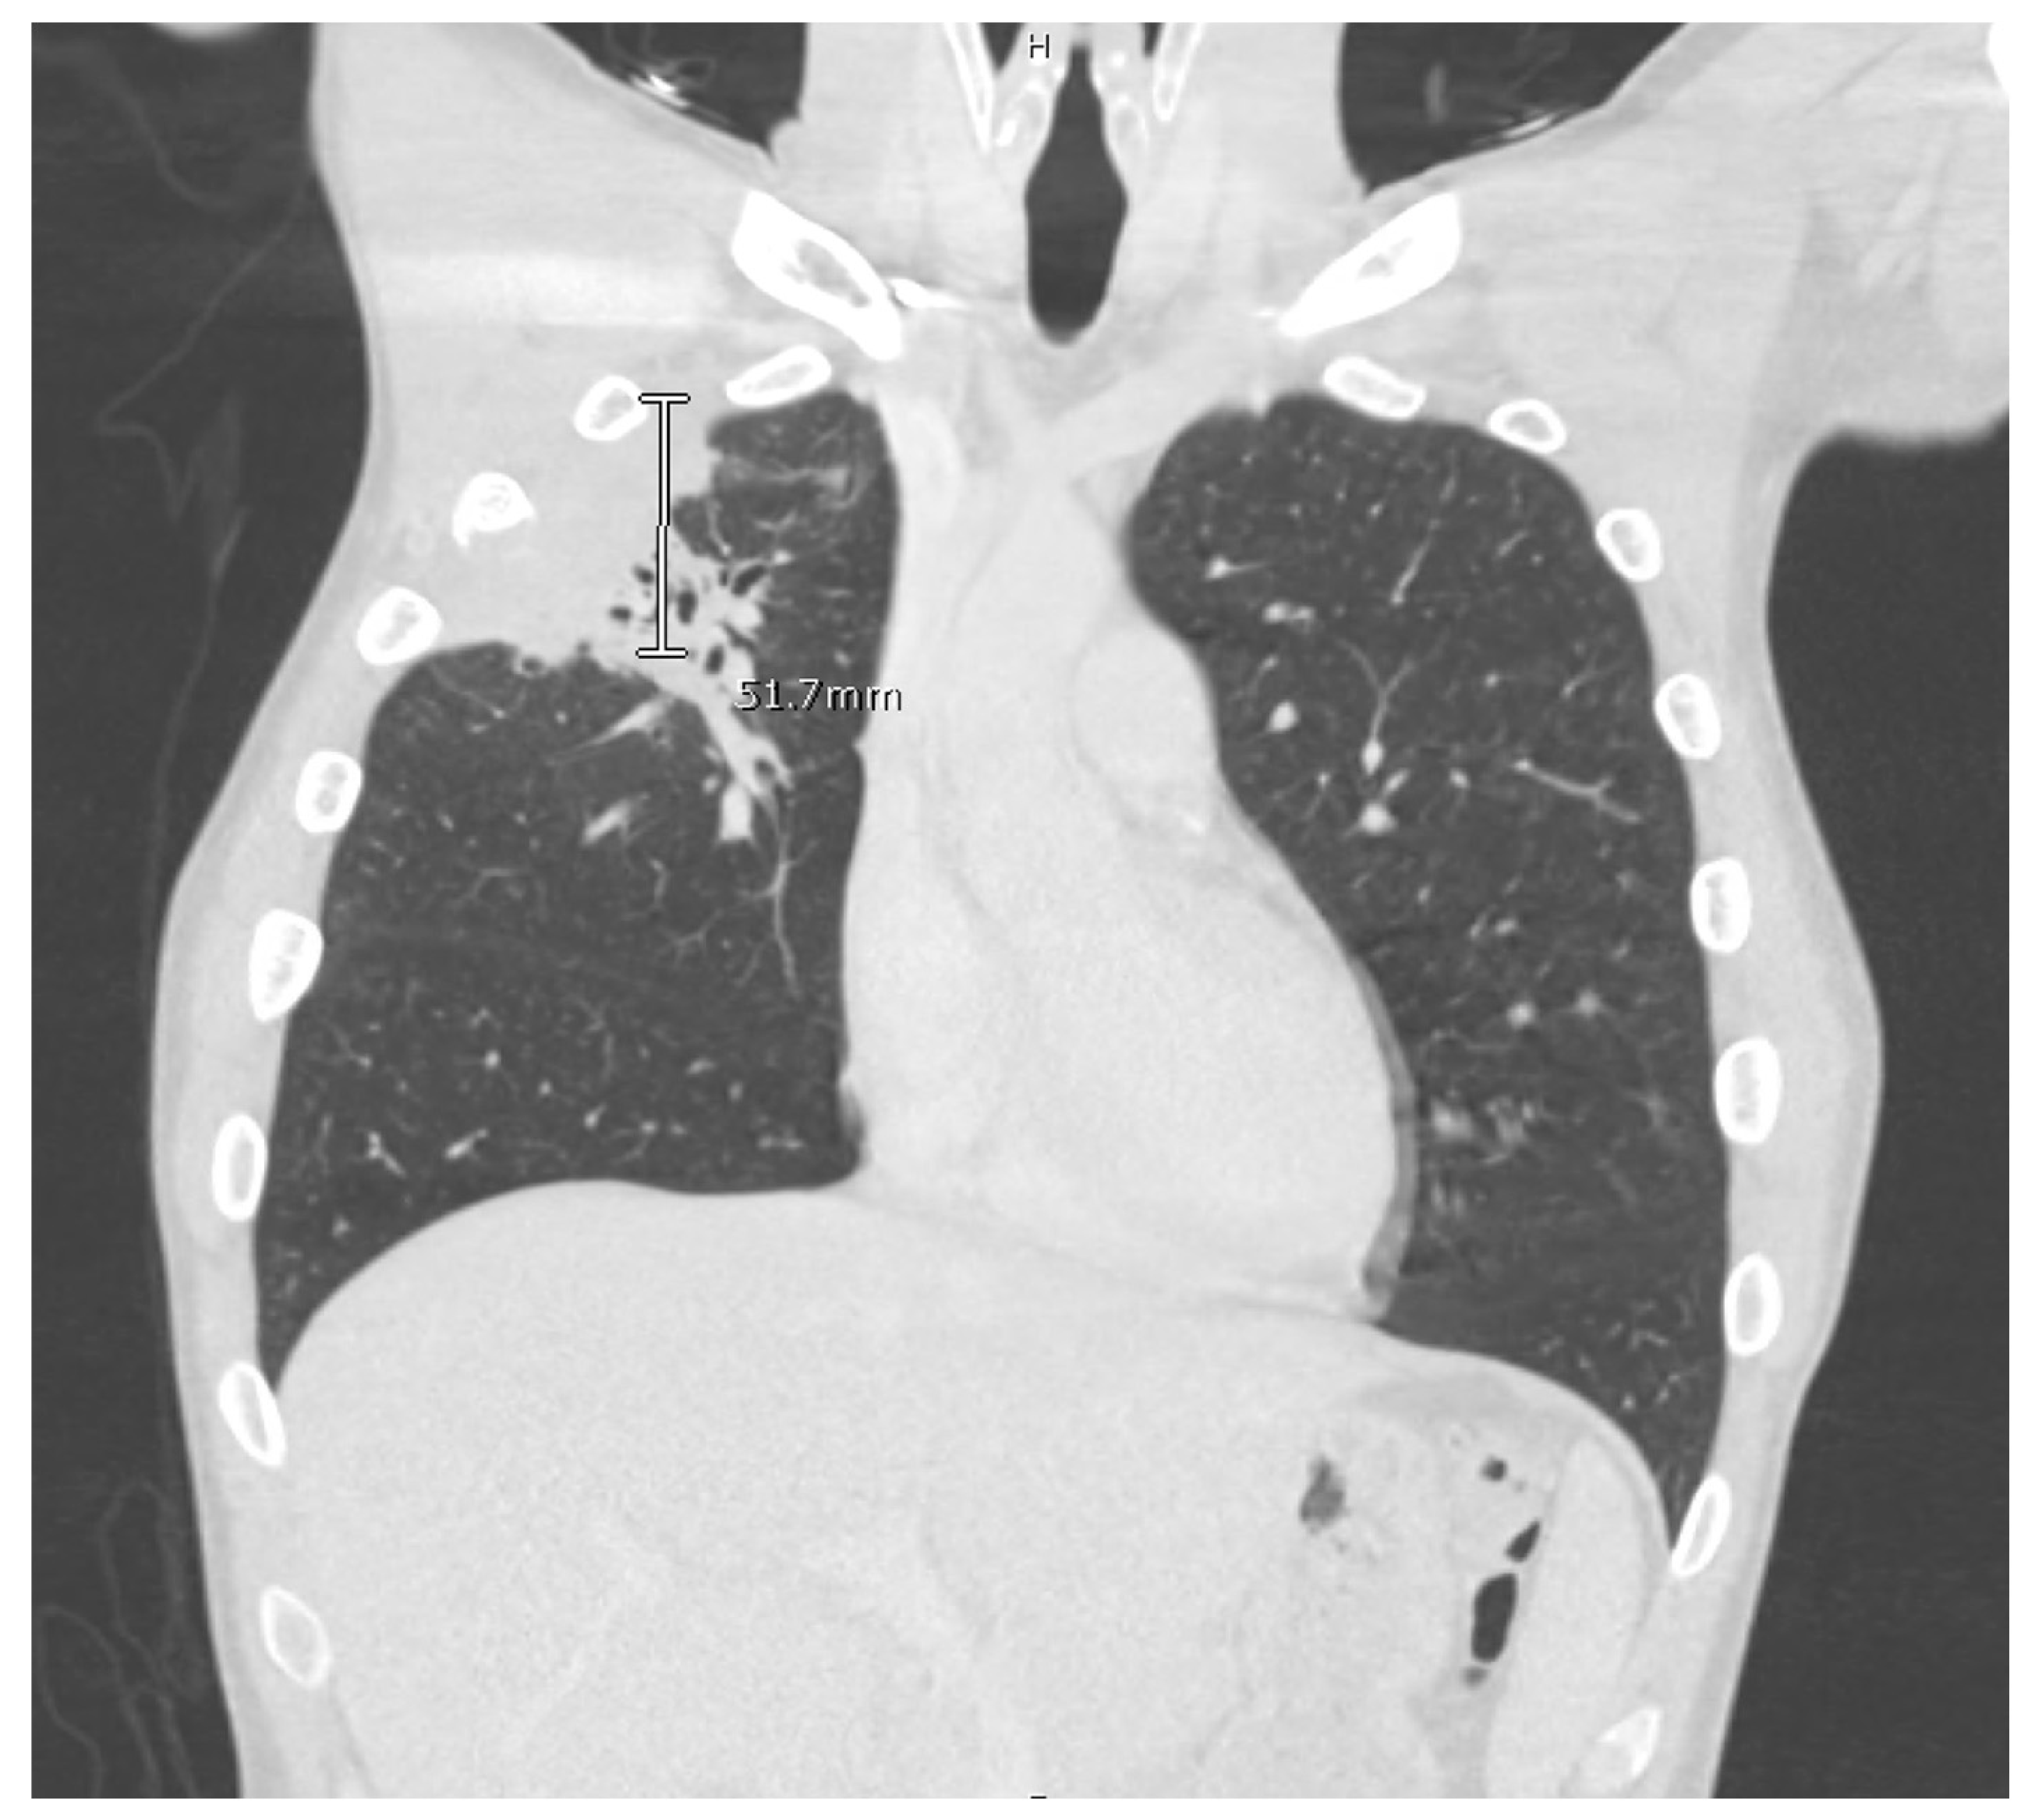

Computed tomography (CT) scan of his chest and abdomen revealed a right upper lobe cavitary lesion abutting the ribs and a sinus tract from his left ischium to the skin over his left lower abdomen (Figure 2). Additionally, a magnetic resonance image (MRI) of his head was obtained which demonstrated a mass extending from his right occipital skull with evidence of skull erosion as well (Figure 3).

Figure 2. CT Chest.